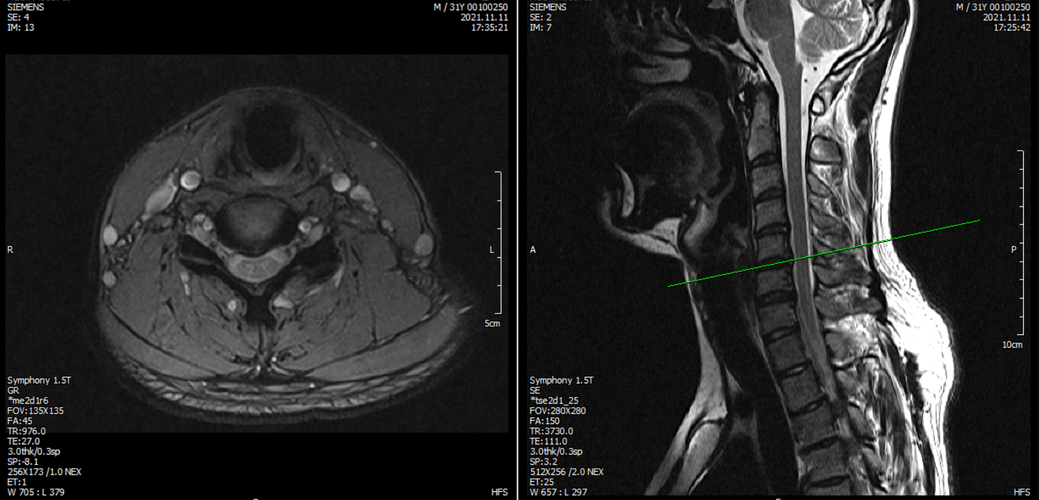

아래는 저의 경추과 요추 MRI 사진 첨부합니다.

• 1번 째 사진

• 2번 째 사진

• 3번 째 사진

• 4번 째 사진

목디스크로 인해 상하지의 힘이 다 빠지려면 척수까지 침범하는 병변이 있어야 합니다.

그런 상황이 아니므로 디스크는 배제해도 되겠습니다.